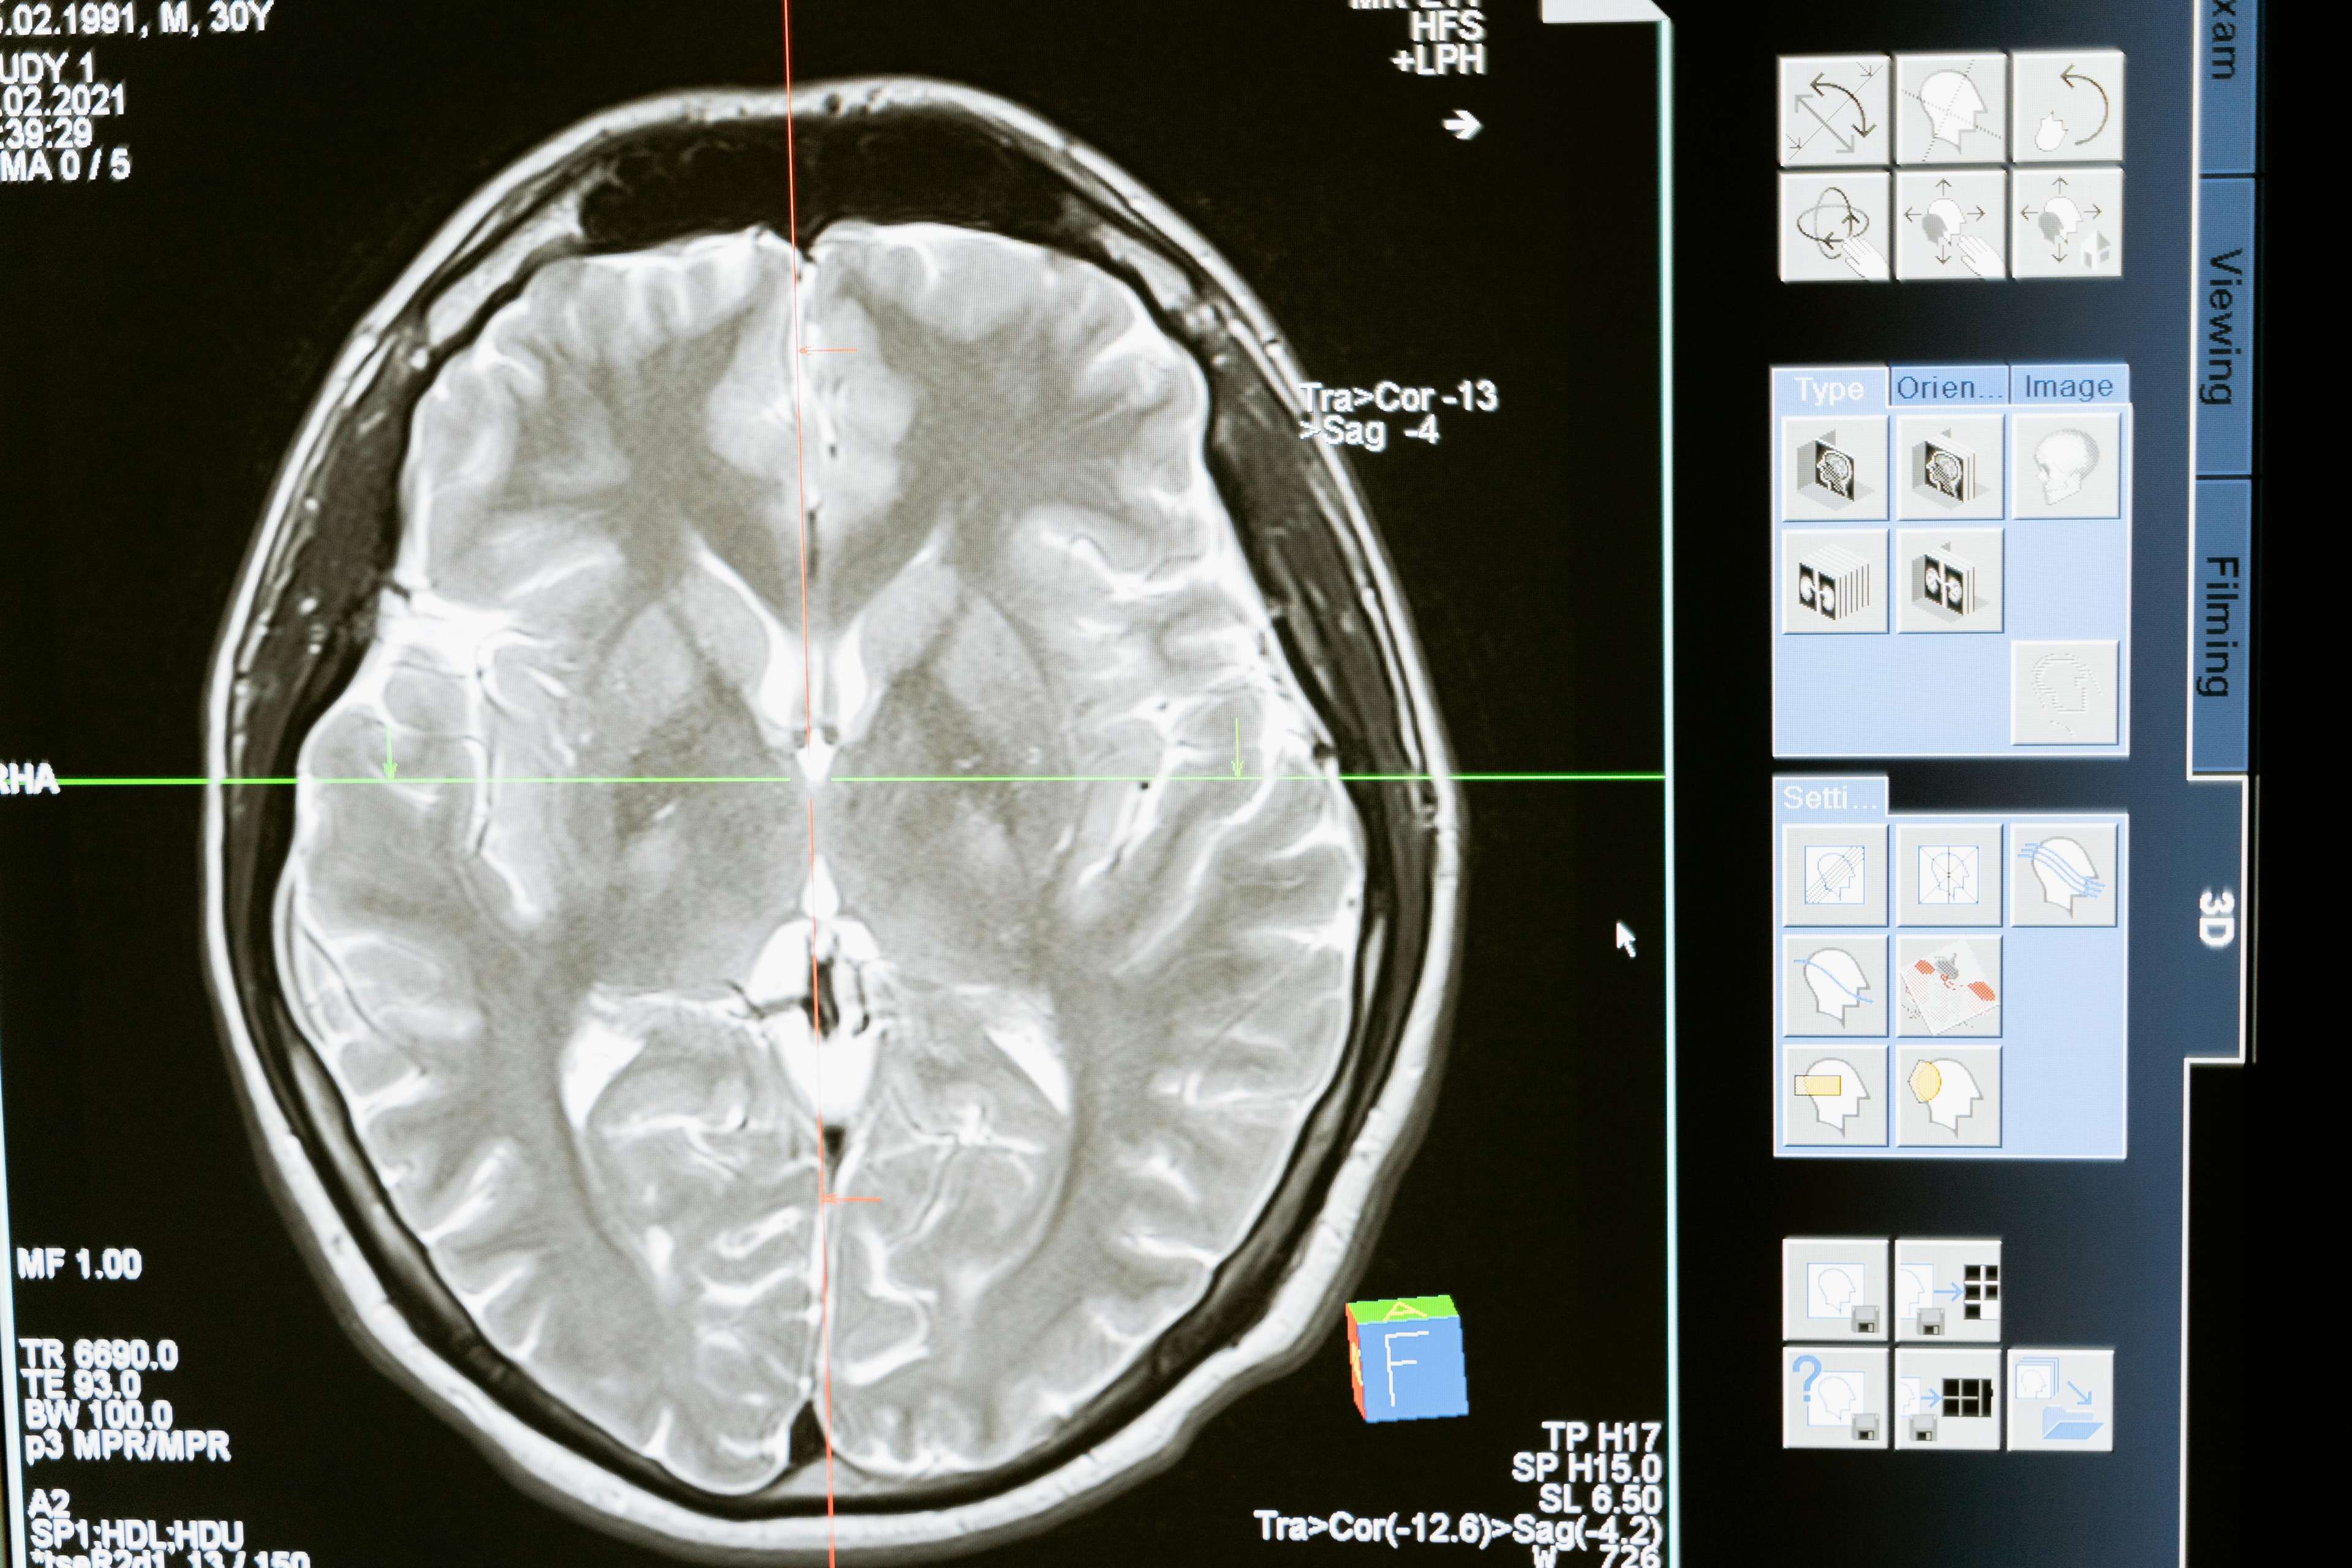

Глубокая стимуляция мозга — это хирургическая процедура, которая включает в себя имплантацию устройства, посылающего электрические импульсы в определенные области мозга. Это инновационное лечение сыграло важную роль в управлении целым рядом состояний, включая болезнь Паркинсона, дистонию, обсессивно-компульсивное расстройство и эпилепсию. Воздействуя на определенные области мозга, глубокая стимуляция мозга может помочь регулировать аномальную мозговую активность, облегчая симптомы и значительно улучшая качество жизни. Результаты не что иное, как замечательные - пациенты, которые когда -то были ограничены своими домами, теперь могут ходить, бегать и жить в полной мере.

Достижения в глубокой стимуляции мозга были быстрыми, с новыми технологиями и методами регулярно появляются. Одним из наиболее значительных разработок является введение направленных лидов, которые обеспечивают более точное нацеливание на области мозга. Это привело к улучшению результатов и снижению побочных эффектов, что делает лечение еще более эффективным. Кроме того, разработка перезаряжаемых устройств увеличила продолжительность жизни имплантата, снижая необходимость частых замены.

Поскольку глубокая стимуляция мозга продолжает развиваться, возможности безграничны. Исследователи изучают новые возможности применения этого лечения, в том числе его потенциал в лечении таких состояний, как депрессия и тревога. Благодаря достижениям технологий, процедура становится менее инвазивной и более эффективной, прокладывая путь к будущему, когда глубокая стимуляция мозга является жизнеспособным вариантом для еще большего количества людей. Являясь лидером в области медицинского туризма, Healthtrip стремится оставаться в авангарде этих разработок, обеспечивая нашим пациентам доступ к новейшим методам лечения и инновациям.